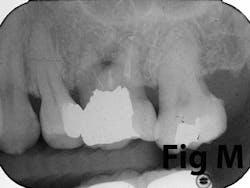

Gingival recession is the result of loss of alveolar bone and tissue, specifically AG. A high number of recession cases result in less than the minimum required amount of AG. (Fig. 4) Similarly, following tooth extraction or long-standing edentulism (without bone preservation), loss of alveolar dimension is accompanied with diminishing AG. (Fig. 5)Note: specific cases may also be attributed to gingival biotype and genetic predisposition.

Surgical reconstruction of a deficient ridge/site begins with bone augmentation (i.e., lateral ridge graft, sinus augmentation, etc.), closely followed by soft-tissue augmentation (i.e., onlay graft, pedicle graft, etc.) When either cannot produce adequate ridge form for esthetics, prosthetic solutions are used to compensate for this deficiency. Soft-tissue augmentation, particularly those procedures to increase AG, is often overlooked.

There is an abundance of literature showing increased gingival inflammation around natural dentition (exacerbated when a fixed restoration is present) when there is less than 2 mm AG. (Figs. 8, 9: post grafting) There is an abundance of literature showing increased incidence of peri-implant mucositis when there is inadequate attached tissue — a weaker connective tissue adhesion and lack of Sharpey’s fibers make the peri-implant tissue even more susceptible to bacterial challenge. (1-6, 8, 10) And as periodontitis is always preceded by gingivitis, peri-implantitis will be preceded by peri-implant mucositis. If we can decrease the incidence of peri-implant mucositis by providing a better and more resilient tissue phenotype, we can lower the incidence of peri-implantitis.The FGG procedure is indicated in cases of implant therapy where this is less than 2 mm of attached tissue present. Sometimes, a FGG is preferred over CTG because: (1) the FGG results in greater gain of attached tissue, (2) the FGG alleviates frenum/muscular pull whereas the connective tissue may increase muscular tension after the flap is coronally advanced, and (3) creeping attachment is often a positive byproduct of the FGG procedure.